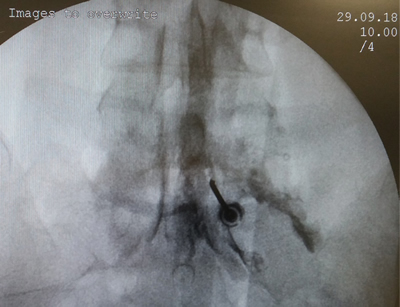

Figura 1

Figura 2